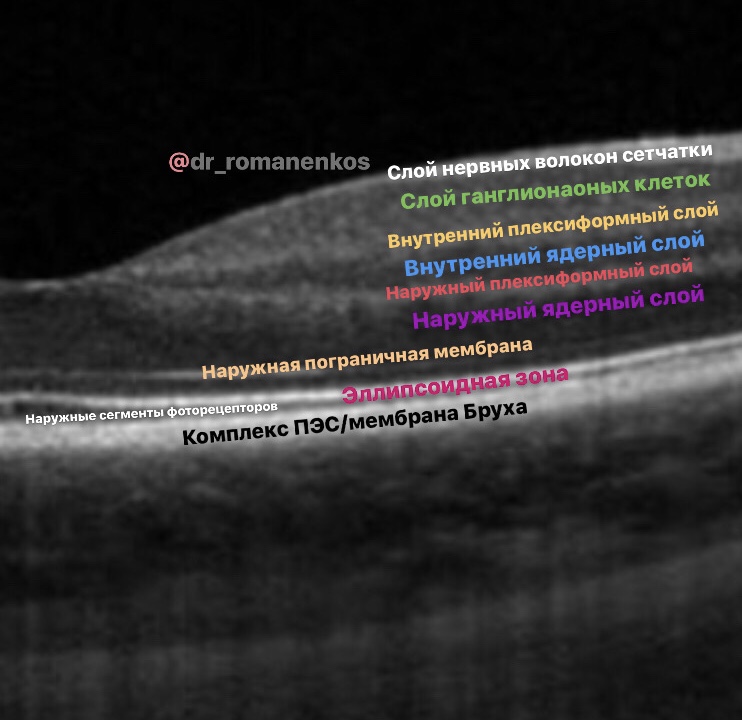

Нам необходимо четкое умение определять анатомические ориентиры, узнавать структуры на ОКТ и видеть патологические изменения - и у НАС оно появится:

1. Мы начнем с основ и принципов самой технологии;

2. Разберем типы сканирования ОКТ, научимся давать качественную и количественную оценку снимкам;

3. В стиле @dr_romanenkos проработаем ОКТ-АНАТОМИЮ глаза;

4. Мы разберем все общие признаки патологий, которые встречаются в оптической когерентной томографии;

5. И самое главное - мы НАУЧИМСЯ ОПИСЫВАТЬ СКАНЫ ОКТ!

Нам необходимо четкое умение определять анатомические ориентиры, узнавать структуры на ОКТ и видеть патологические изменения - и у НАС оно появится:

1. Мы начнем с основ и принципов самой технологии;

2. Разберем типы сканирования ОКТ, научимся давать качественную и количественную оценку снимкам;

3. В стиле @dr_romanenkos проработаем ОКТ-АНАТОМИЮ глаза;

4. Мы разберем все общие признаки патологий, которые встречаются в оптической когерентной томографии;

5. И самое главное - мы НАУЧИМСЯ ОПИСЫВАТЬ СКАНЫ ОКТ!

- видео, сканы ОКТ с обозначениями, фото глазного с разбором на детали, аудисопровождение, текст и, конечно, ОБУЧАЩИЕ ТЕСТЫ